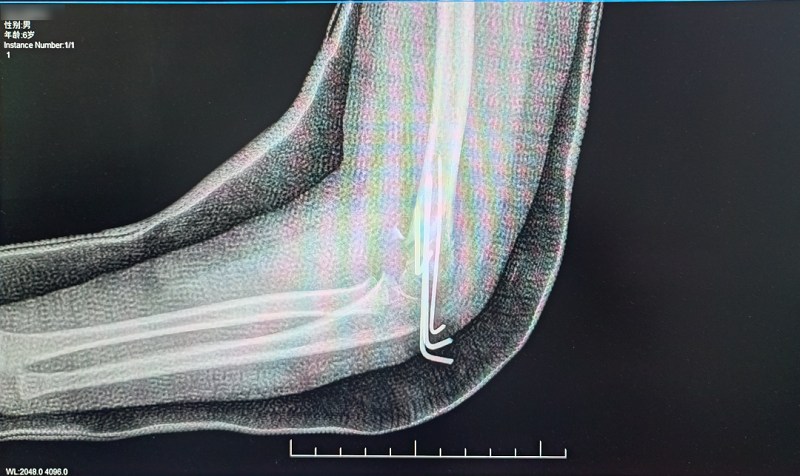

经过对垚垚的细致查体,考虑左肱骨髁上骨折并神经损伤,经团队协商,决定予以中医正骨手法复位经皮穿针治疗。

晚上11点,在麻醉科和小儿骨科团队的默契配合下,30分钟就顺利为垚垚完成复位,同时予以固定,垚垚疼痛明显减轻,李女士也终于长舒了一口气。目前,垚垚仍在住院观察,一周后即可出院。

(术后X光图)